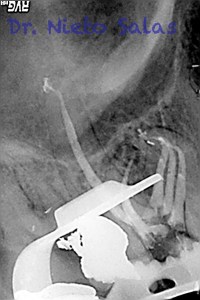

Os presento unos casos de varios molares superiores, con tres conductos mesiovestibulares con un foramen o con dos.

Una vez que tenemos medidas, obturamos los conductos: